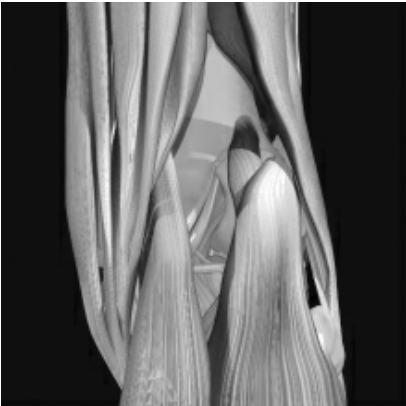

膝关节后侧肌腱

①腓肠肌内侧头;②跖肌起点;③腓肠肌外侧头;④胫侧副韧带(膝内侧);⑤斜韧带;⑥腓侧副韧带(膝外侧);⑦鹅足(由缝匠肌、股薄肌和半腱肌的止点共同组成,其位置稍靠膝内侧);⑧肌止点;⑨股二头肌止点